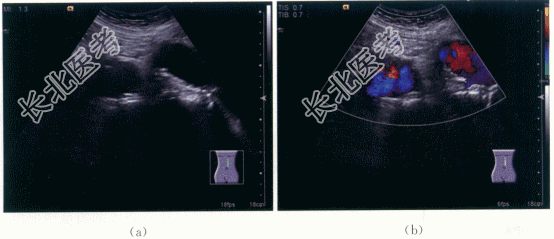

患者,男性,80岁,因“体检发现中上腹部肿块伴搏动感”就诊,有高血压病史20年,既往血压控制较差。否认糖尿病病史、冠心病病史等其他慢性疾病史。否认手术外伤史。

患者中上腹部触及一肿块,大小约5cm×4cm,边缘光滑,质地软,可推动,触之有搏动感。血压200mmHg/120mmHg。

二、影像资料及诊断

1.影像资料

腹主动脉及双侧髂动脉多发动脉瘤形成。